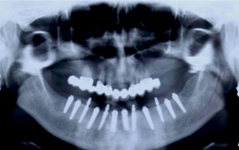

• Zavedení implantátu do kosti čelisti

• Zahojení do kosti – 3-4měsíce(v některých případech i déle – doplňování kosti)

Zavedení implantátů do kosti je většinou ambulantní chirurgický výkon, srovnatelný s vytržením zubu a většinou se provádí v lokální anestézii. Ve výjimečných případech je možné použít i analgosedaci či celkovou narkózu. Operaci provádí zubní lékař-implantolog při dodržení všech podmínek sterility pro operaci. Nástroje pro tuto operaci jsou konstruovány tak, aby výkon byl šetrný vůči kosti a zavedení implantátu bylo provedeno ve velmi krátké době. Díky kvalitní anestézii je výkon nebolestivý. Aby byl pooperační otok co nejmenší, je potřeba operovanou oblast chladit, dle poučení ošetřujícího lékaře. Lékař také ordinuje podle potřeby léky na bolest, případně antibiotika.

Průměrná doba hojení implantátů před provedením definitivního protetického ošetření je 3-4 měsíce, v případech, kde je nutné doplnit chybějící kost (různé metody, postupy a materiály) – tzv. augmentace) se může doba hojení prodloužit na 8-12 měsíců. S tím je pacient vždy předem seznámen svým lékařem.